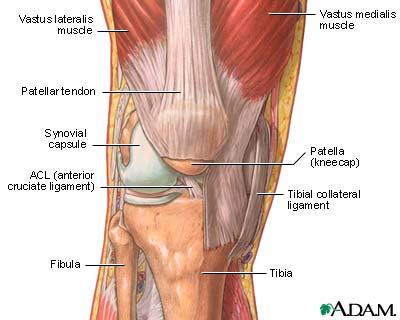

The structure of a joint

Joints, particularly hinge joints like the elbow and the knee, are complex structures made up of bone, muscles, synovium, cartilage, and ligaments that are designed to bear weight and move the body through space. The knee consists of the femur (thigh bone) above, and the tibia (shin bone) and fibula below. The kneecap (patella) glides through a shallow groove on the front part of the lower thigh bone. Ligaments and tendons connect the three bones of the knee, which are contained in the joint capsule (synovium) and are cushioned by cartilage.